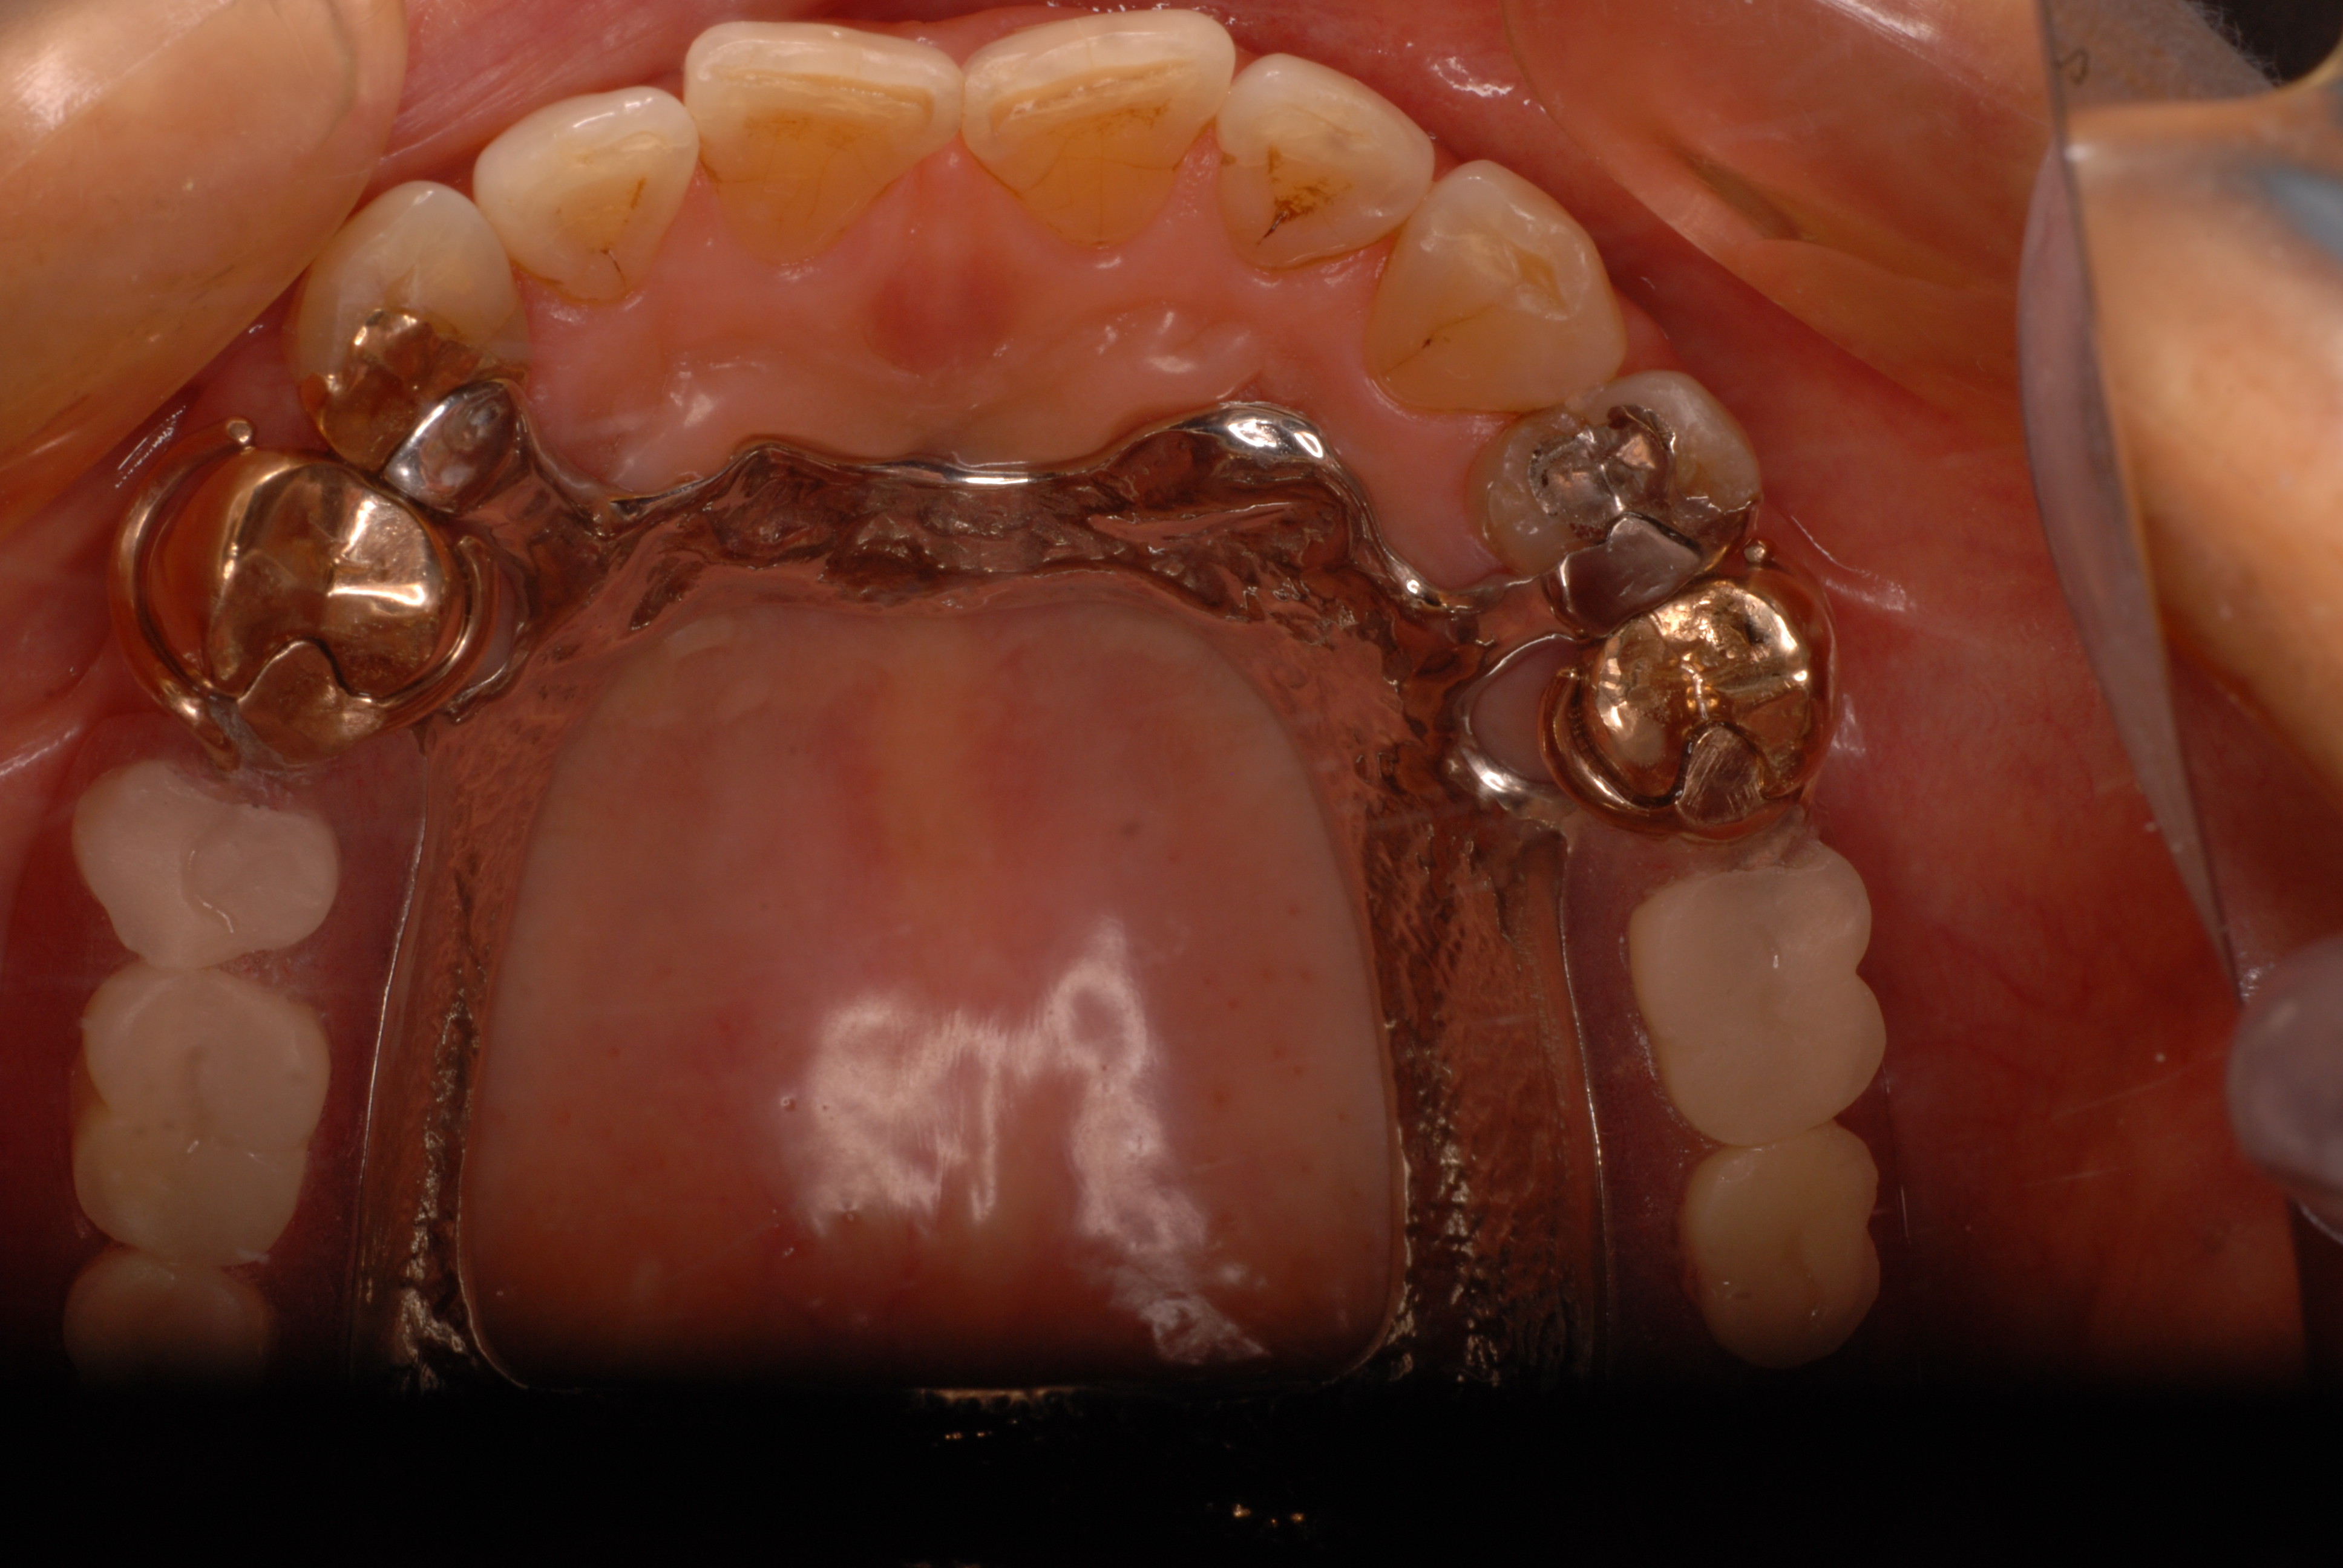

以前やりました上の歯です。

数か月前に新規で初めて部分入れ歯を入れた方が定期的健診に来られました。

上の歯が少なくよく噛めません。そして写真右上の歯が使いすぎてしみるのです。

DSC_0026

写真の左上の部分の歯茎が痛いそうです。

DSC_0003

調べたところ入れ歯を外して磨いていないので歯周病を起こしていました。

何かを入れたり入れ歯を入れたりすると必ずばい菌が溜まりやすくなるのです。

入れてから或いは、被せてからしばらくは歯周病になっていないか確認し続けないと危険です。

最終的には、空隙を開けた入れ歯から全面的に大きくした入れ歯にして

歯に無理がかかるのを防ぎました。発音の心配をしていたのですが、問題ありませんでした。

見た目には、正面からでも入れ歯はわかりませんね。

ただ金属が接触しているところはばい菌が溜まりやすいのです。

要注意です。

写真で、左上の部分の歯の間に強い炎症があります。